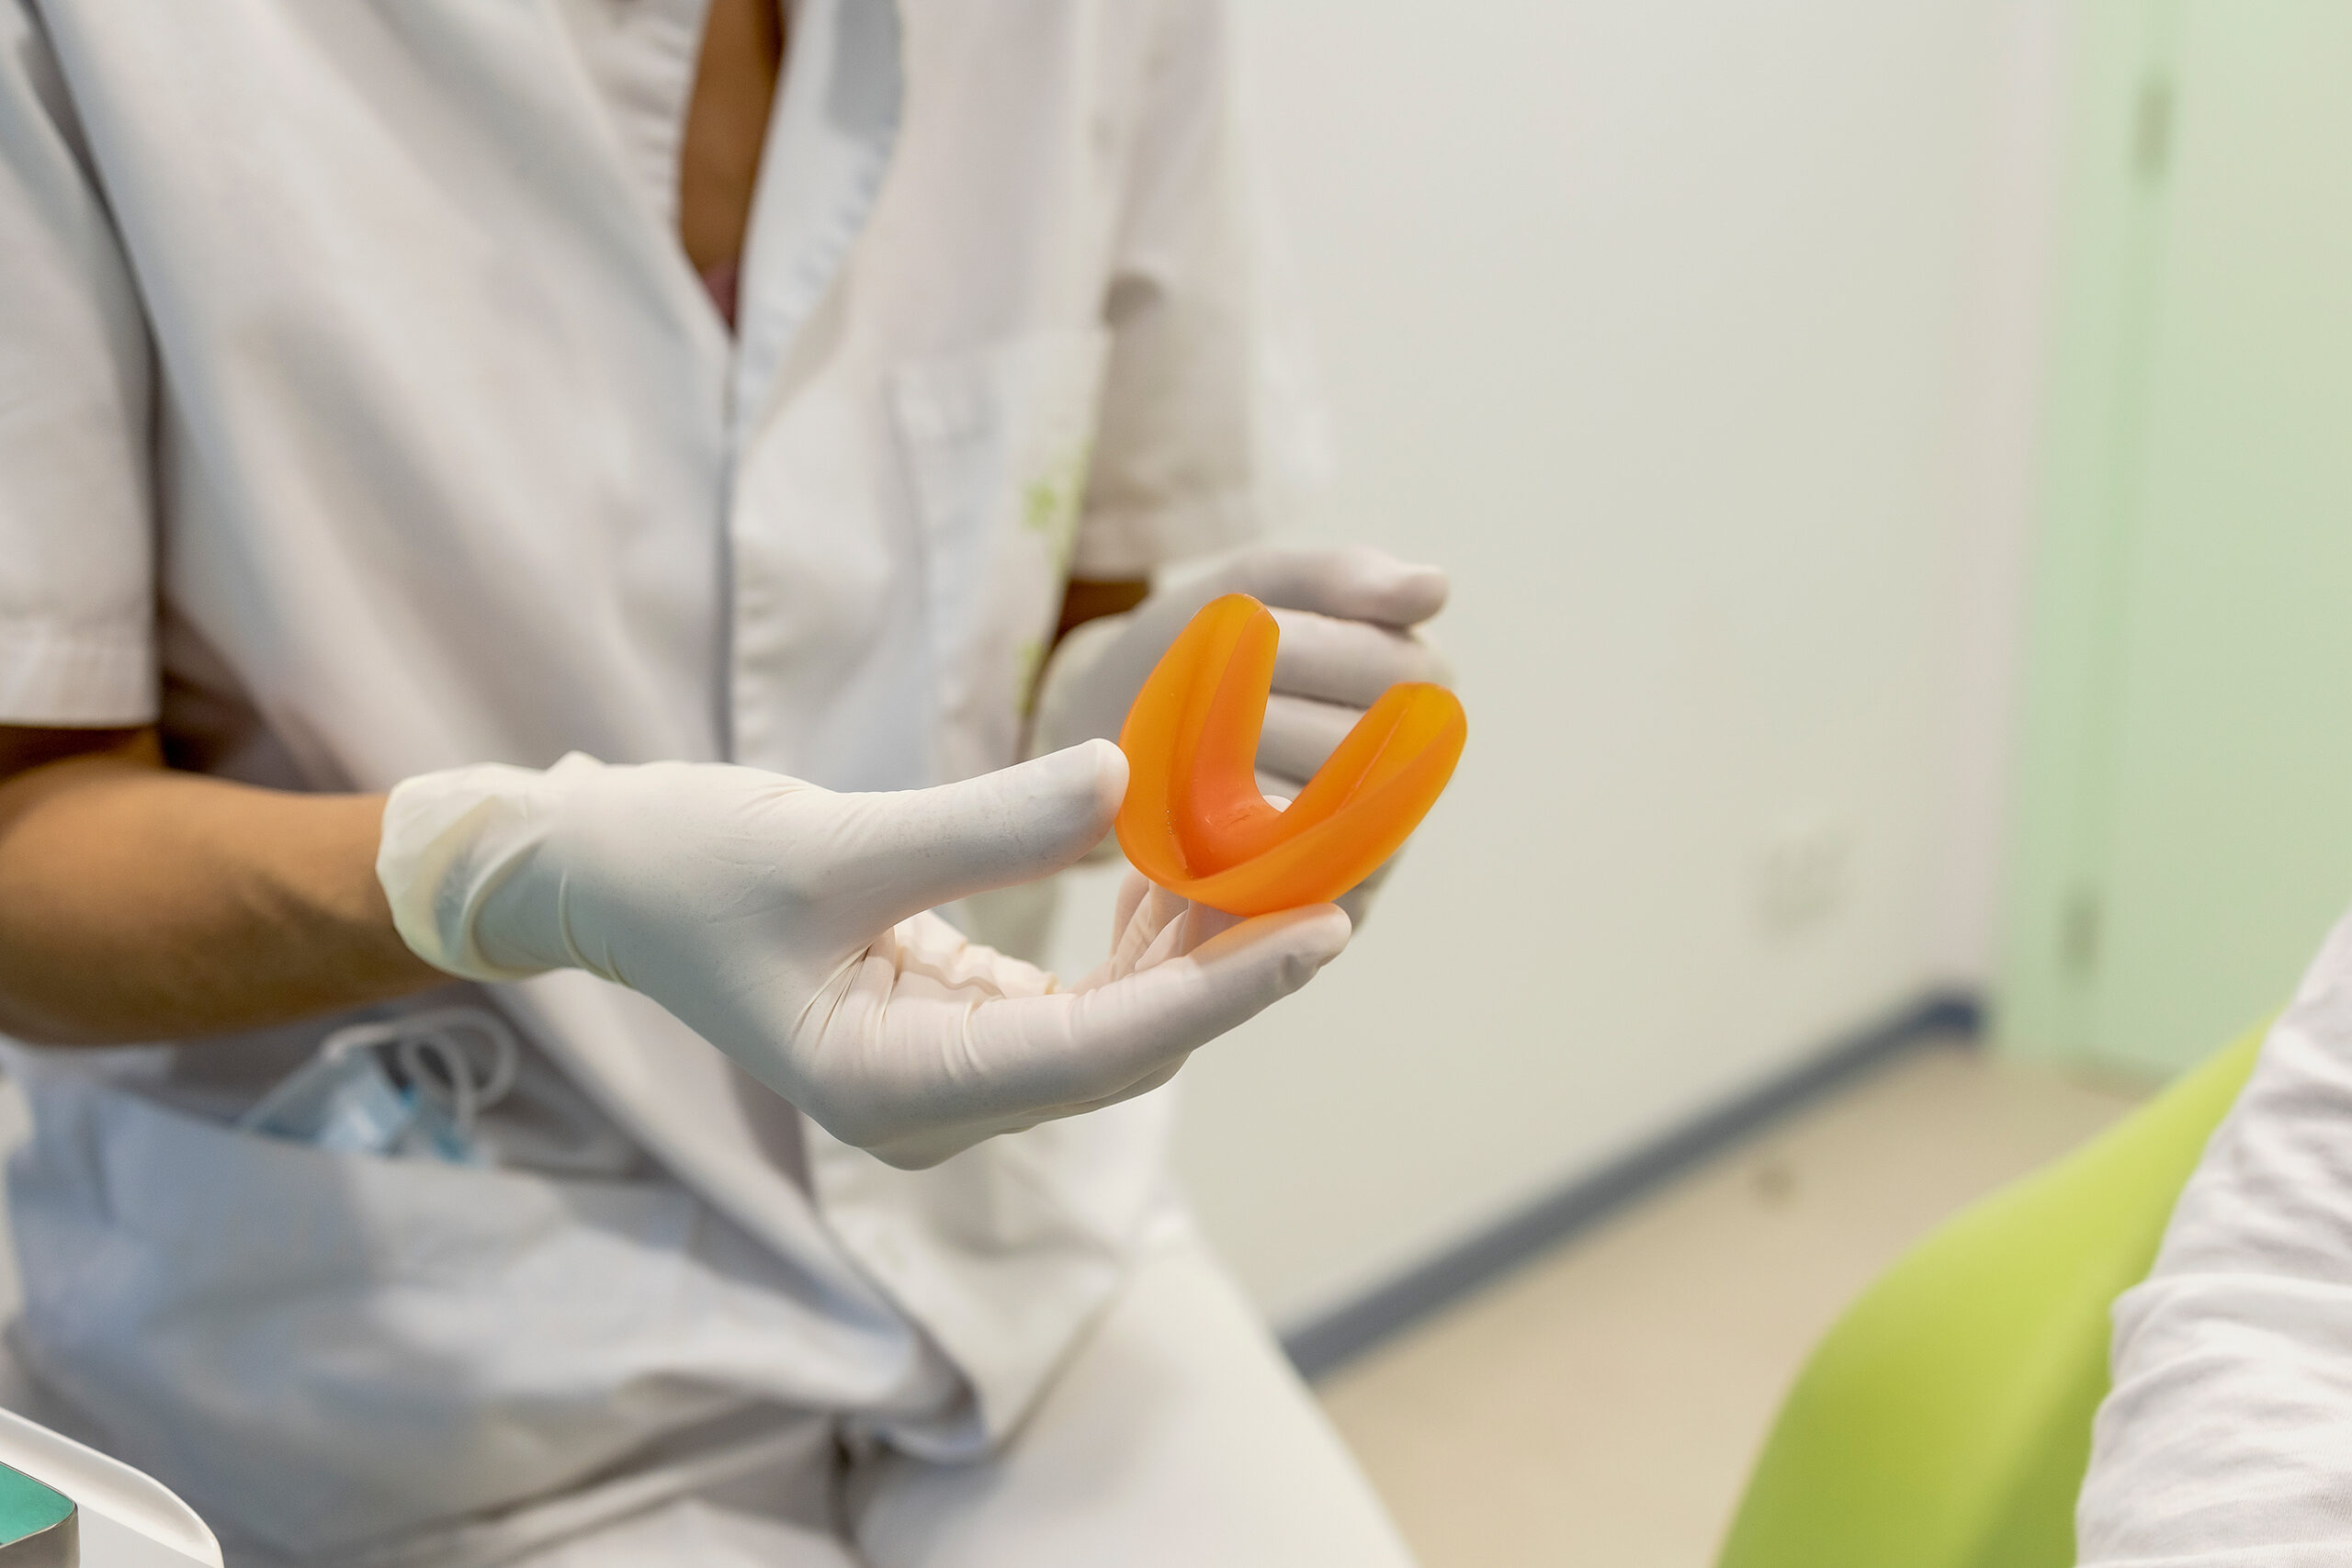

En tots els casos el tractament es basa principalment en portar un aparell anomenat activador plurifuncional: aquesta fèrula es col·loca a la boca durant tota la nit i també durant algunes estones del dia per fer un treball més conscient.

Mentre la portem posada, ens obliga a respirar exclusivament pel nas i també impedeix que la llengua es col·loqui contra o entre les dents a l’hora d’empassar, això requereix d’un cert entrenament per alguns individus que no tenen l’hàbit integrat, per això sempre us acompanyarem de manera personalitzada amb la intervenció de professionals especialitzats en cada una de les funcions a tractar.

Per altra banda, mentre portem la fèrula posada també podem sentir com la mandíbula queda més relaxada ja que ens ajuda a col·locar-la en una posició de descans i desprogramació a nivell articular, cosa que també ens ajuda a tractar problemes d’ATM (articulació temporo-mandibular), tensions de cervicals (molt relacionades amb l’ATM) i moltes altres afeccions de tipus postural o músculo-esquelètic.

Un activador plurifuncional ens obliga a col·locar correctament la llengua però quan el portem només durant la nit de manera inconscient no estem reeducant l’hàbit de manera veritable, cal fer-ho de manera proactiva i durant el dia.

L’activador plurifuncional que oferim en aquests casos ens procura un augment de dimensió vertical de la boca, això fa que al cap del temps es reposicioni la mandíbula en una posició molt més fisiològica, generant més espai a l’articulació temporomandibular i facilitant els moviments de lateralitat per mastegar. Això es tradueix en una reducció de les tensions tant musculars com articulars de la zona de cap i coll i també en un a reducció del dolor. Paulatinament també es va transmetent aquest canvi a la resta del cos i el consultant experimenta canvis de postura.